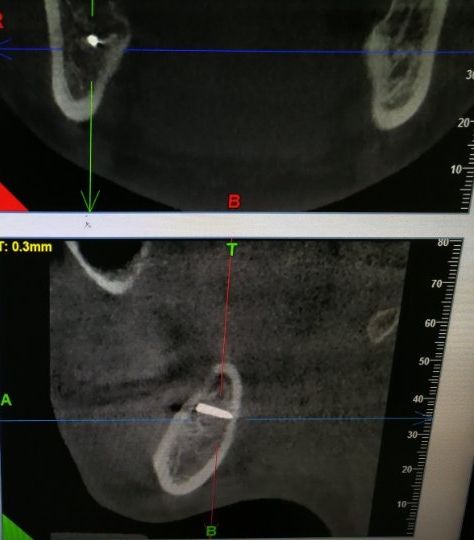

李女士口腔内的金属物。这一检查,把她吓了一跳。据其在松岗人民医院口腔科拍摄的x光片显示:她之前拔掉的智齿牙窝里,残留了两节金属物,并且已经没入很深,快要接近下颌神经管了。如果再深一点,可能会导致其面部神经损坏。“我听到,差点吓哭了。”李女士说。自己当时因为想省点钱,就去了小诊所,没想到竟然发生了这样的事情。好在后来去医院还算及时,医护人员确定位置和异物大小等情况后,利用超声骨刀把李女士牙窝中的异物取了出来。后经十余天的输液治疗,李女士的情况已经基本恢复。

取出的金属物长约1公分。那么,嵌入李女士牙窝中的金属物质到底是什么呢?松岗人民医院口腔科医生石健介绍,医院接诊后,为患者拍摄了X光片。从X光片可以看到,李女士拔牙创口有一个密度很高的金属影,长度约1公分。经联系李女士拔牙的诊所医生了解到,这个异物可能是拔牙用具“压挺”的尖端碎片。“牙挺是靠撬力来拔出牙齿的,医生如果用力不当,有时会将牙挺尖端折断,遗留在患者的牙窝内。”石健医生说。据介绍,因异物嵌入很深,快要接近神经管,取出时风险较大。后经商议,决定使用超声骨刀帮患者将异物取出。李女士表介绍,事发后,当时为其拔牙的小诊所对此进行了道歉和赔偿。